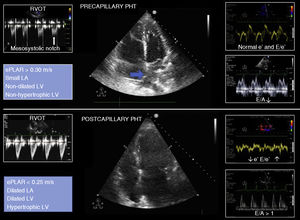

Precapillary vs postcapillary pulmonary hypertensionThe most common cause of RV failure is PHT, defined as PAPm ≥ 25 mmHg.29 The analysis of TI allows us to estimate PHT, with VmaxTI ≤ 2.8 m/s being associated with a low probability of PHT, while VmaxTI > 3.4 m/s is associated with a high probability of PHT (Fig. 5).

Diagnosing the cause of PHT is crucial to define the appropriate treatment. In this regard, a first step is to determine whether the underlying cause is precapillary, with pulmonary capillary pressure (PCP) (wedge pressure) ≤ 15 mmHg, or postcapillary due to pathology of the LV, with PCP ≥ 15 mmHg. The echocardiographic findings suggestive of a pre- or postcapillary etiology are described in Fig. 6.29 The calculation of PVR contributes to establishing the differentiation.30

Echocardiographic signs suggestive of pre- and postcapillary pulmonary hypertension. The blue arrow indicates the interatrial septum bulging towards the left atrium. LA: left atrium; ePLAR: echographic pulmonary to left atrial ratio = [VmaxTI/(E/eʹ) mitral]; PHT: pulmonary hypertension; RVOT: right ventricle outflow tract; LV: left ventricle.

An invasive parameter that has been shown to be useful in differentiating between pre- and postcapillary PHT is the transpulmonary gradient, defined as the difference between PAPm and the pressure of the LA, estimated from the PCP.46 A value of > 12 mmHg is indicative of a precapillary origin. Recently, a surrogate indicator of the transpulmonary gradient has been proposed in the form of the echographic pulmonary to left atrial ratio (ePLAR) measured from the relationship between VmaxTI, as an estimate of pulmonary pressure, and the mitral E/eʹ ratio, as an estimate of the pressure of the LA. In this regard, ePLAR > 0.30 m/s would be indicative of precapillary PHT, while < 0.25 m/s would be indicative of postcapillary PHT.46